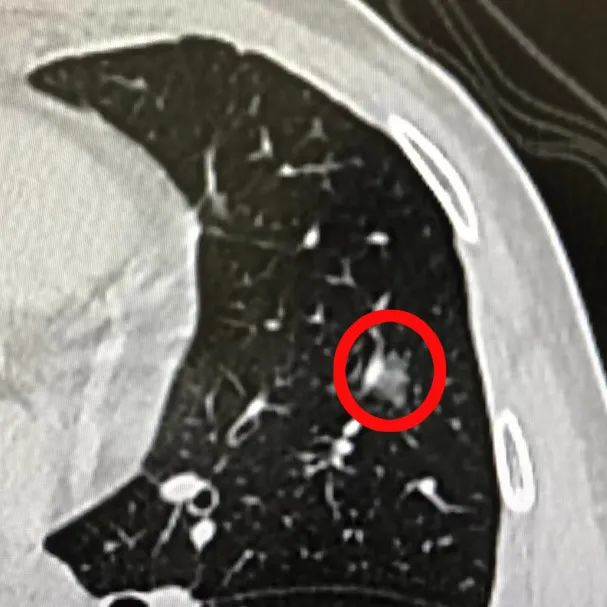

今年 1 月,王先生体检时发现左肺上叶存在一个 9 mmx8 mm 磨玻璃结节,3 月后复查 CT,提示病灶大小稍有增加,不排除恶性可能,需要尽快手术切除。

「早期肺癌通常表现为肺部小结节,精准定位是肺小结节切除的关键。」据浙大四院心胸外科杨泽山主任医师介绍,肺小结节的定位,目前主要方法为术前 CT 引导下经皮穿刺金属钩定位,由于调整穿刺针通道的需要,患者需要多次射线暴露。

电磁导航气管镜通过术前的高分辨 CT 扫描为患者定制个体化支气管树地图,磁探头根据预先设定规划的导航路径,配合超细操作导管,精准地到达常规支气管镜无法到达的部位,可以「无死角」地对病变处进行观察、标记和活检取样。